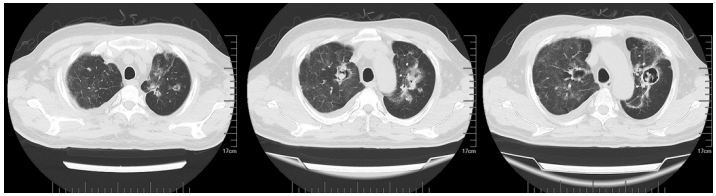

2023年5月28日胸部CT:左上肺实变,少量胸腔积液(图8)

图8  患者胸部CT(2023-05-28)

经过近1个月的治疗,复查胸部CT可见双肺病灶明显吸收(图9)。7月30日随访见肺内仅余结节样病灶及纤维条索影(图10)

图9  患者胸部CT(2023-06-09)

图10  患者胸部CT(2023-07-30)